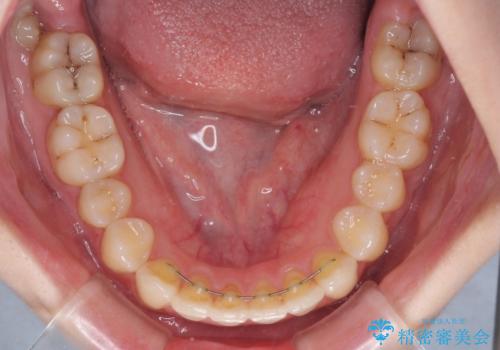

- 上下前歯のデコボコを気にして来院された患者様です。

以前矯正をした後戻りということで、歯列不正はそれほど大きくなかったため、インビザライン・ライトを用いて矯正治療を行うこととしました。

インビザラインは1日に22時間を目安に装着していただきますが、装着時間が十分でないとシミュレーション通りに動かないことがあります。

前歯のデコボコが残っており、シミュレーション通りに動いていない部分がありましたが、再矯正であることやご本人の満足いくところまでデコボコが改善されたとのことで、治療を終了することとしました。